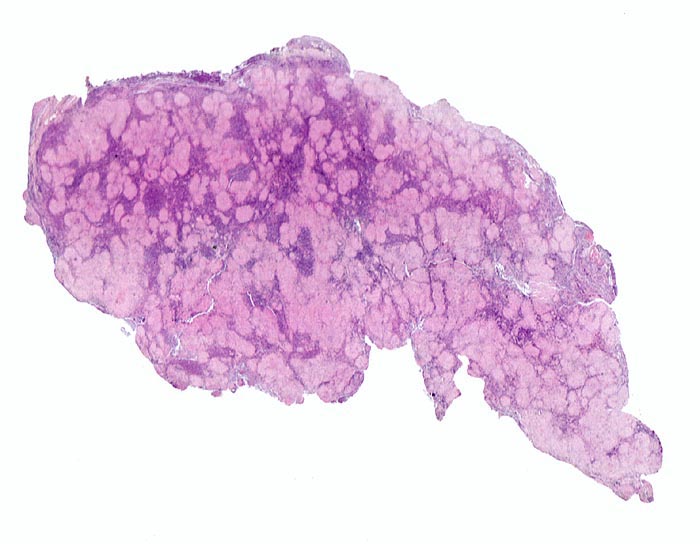

Sarkoidosegranulome bestehen aus Epitheloidzellen mit einem peripheren Lymphozytensaum. Mehrkernige Riesenzellen, meistens solche vom Langhans-Typ mit hufeisenförmig angeordneten Kernen und Asteroidkörperchen (> 4173) können zusätzlich vorhanden sein. Diese Granulome enthalten meist keine Nekroseherde (=produktives Granulom). Man findet diesen Granulomtyp hauptsächlich in Lymphknoten, aber auch in inneren Organen und in der Haut. Die Sarkoidosegranulome zeigen in späteren Stadien eine charakteristische perigranulomatöse und die Granulome septierend unterteilende Fibrose (> 4015).

• Wenig erhaltenes Lymphknotengewebe (blau).

• Konfluierende Granulome aus grossleibigen Epitheloidzellen.

• Perigranulomatöse Fibrose. Das sollte der Kliniker dem Pathologen mitteilen: